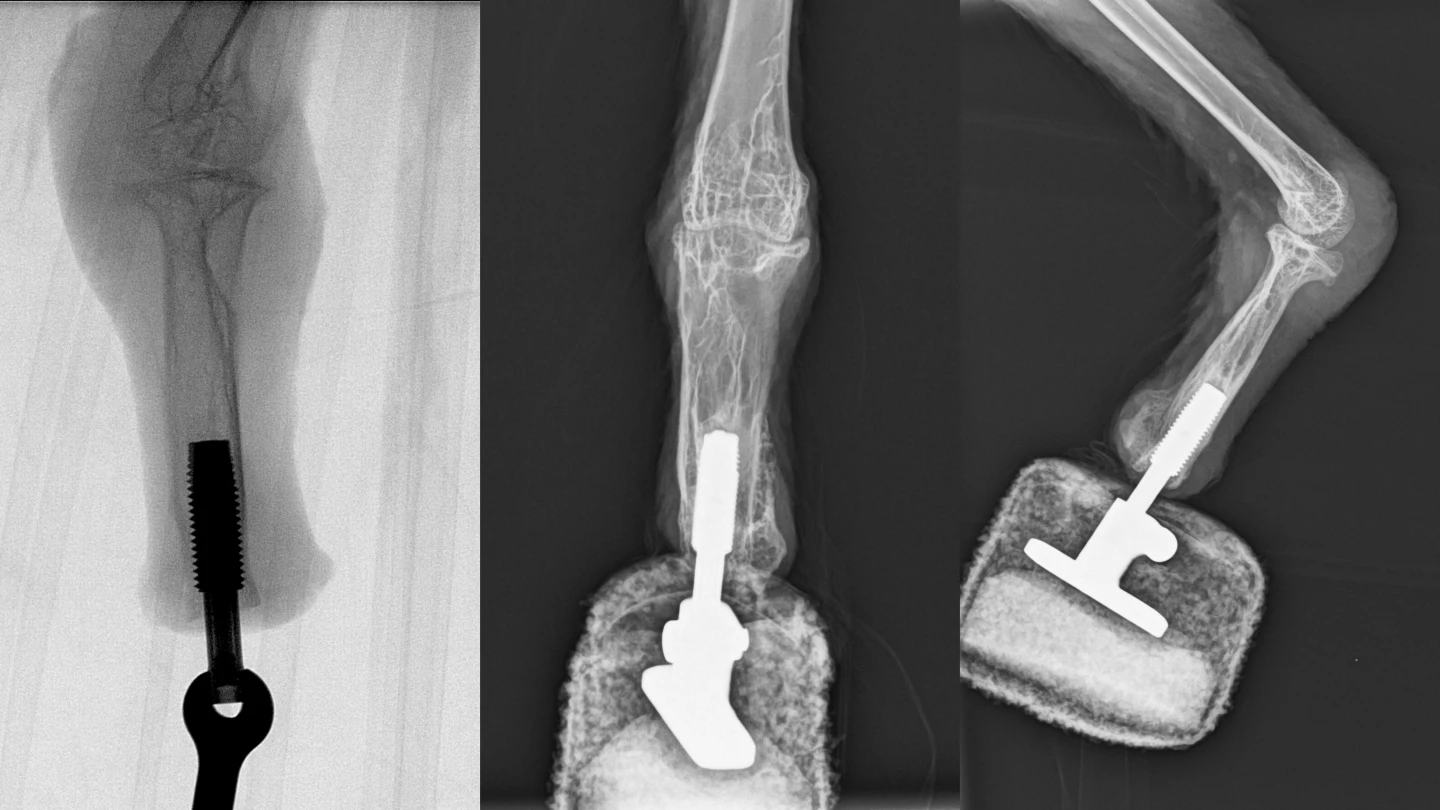

For the vulture, the team utilized a process known as osseointegration, in which the base of the artificial foot was joined directly to the end of the leg bone in the bird's residual stump. Mia began attempting to walk within three weeks of the surgery, and was putting her full weight on the foot after six weeks. She is now reportedly walking and landing normally.

"This concept offers a high degree of embodiment, since osseoperception provides direct intuitive feedback, thereby allowing natural use of the extremity for walking and feeding," says Aszmann. "For the first time we have now successfully bionically reconstructed the limb of a vulture."